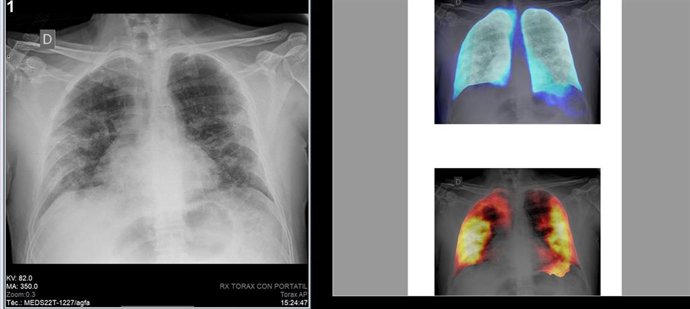

Archivo - Técnicas de Inteligencia Artificial en radiografías de tórax

Archivo - Técnicas de Inteligencia Artificial en radiografías de tórax - GVA - Archivo